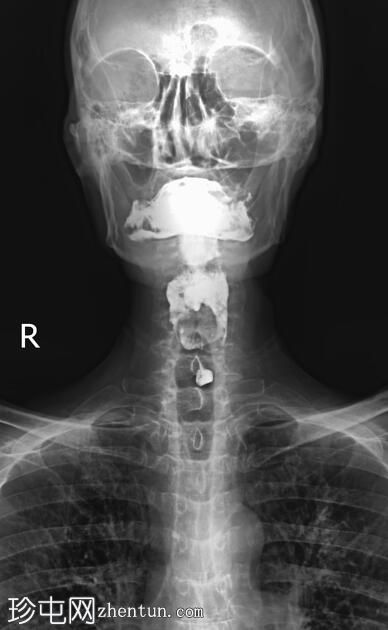

正位

正位和侧位图像显示造影剂在咽部积聚,并伴有钡剂误吸至气道和支气管树。未见

肺

实变。

此外,胸椎存在退行性改变,表现为终板硬化和边缘骨赘形成。

透视图像显示钡剂误吸覆盖喉部和气管支气管树。